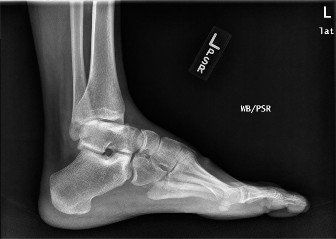

A 32-year-old, professional ballet dancer presents with right ankle pain. She reports that she has had severa…